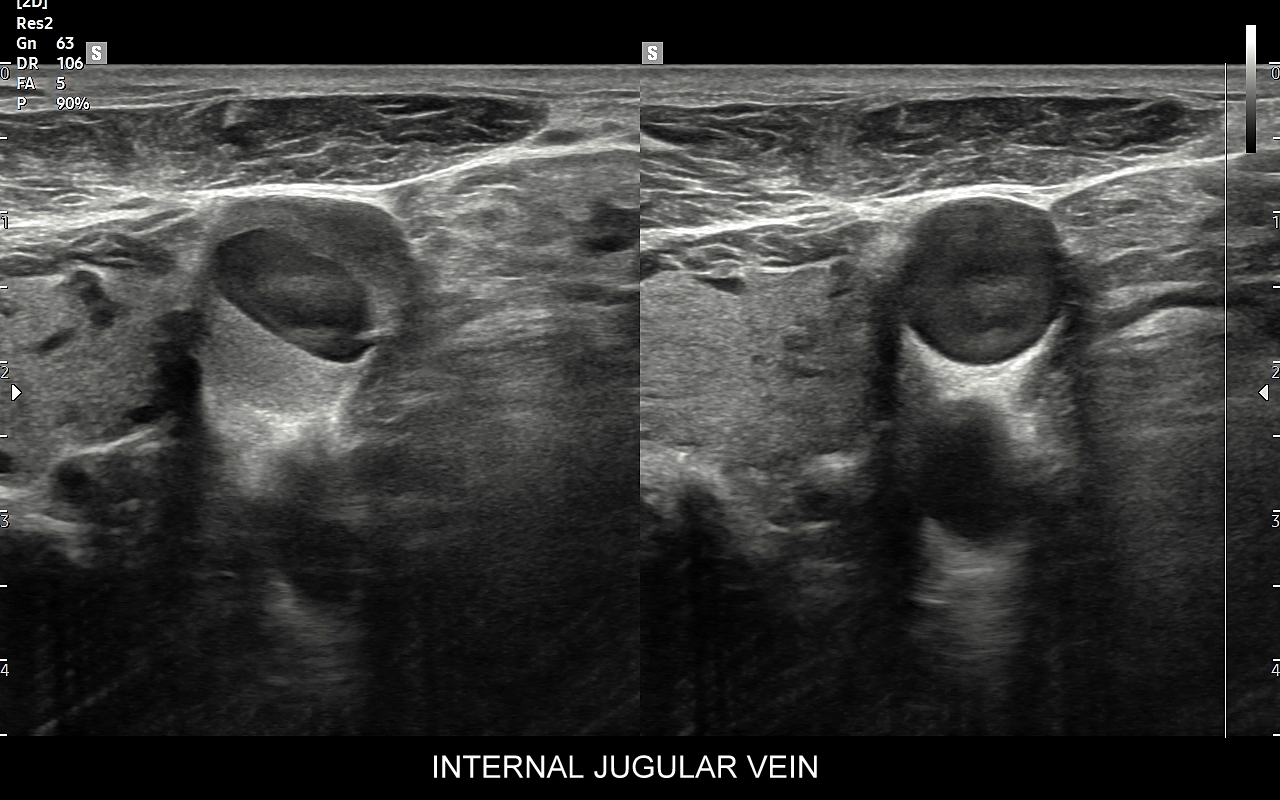

Czym jest zakrzepica żył? Zakrzepica żylna polega na powstaniu skrzepu wewnątrz naczynia żylnego i wtórnym rozwoju stanu zapalnego w okolicy naczynia. Choroba dotyczyć może układu powierzchownego żył lub żylaków, a w tym wypadku nie jest zwykle stanem niebezpiecznym; a także układu głębokiego żył, co z kolei jest stanem potencjalnie zagrażającym życiu, gdyż może sprowokować zatorowość płucną. Zakrzepica żył głębokich (ang. deep venous thrombosis DVT) częściej występuje w obrębie żył kończyn dolnych, następnie w obrębie żył biodrowych, rzadziej w żyle podobojczykowej i żyłach głębokich kończyny górnej. Przyczyny zakrzepicy żylnej są różnorodne i obejmują m. in. długie podróże, długotrwałe unieruchomienie, operacje ortopedyczne, chirurgiczne i szczękowe, urazy tkanek miękkich oraz złamania kości, genetycznie uwarunkowane trombofilie, nowotwory złośliwe, odwodnienie, infekcje miejscowe i ogólnoustrojowe. W przypadku zakrzepicy żyły podobojczykowej klasyczną jej przyczyną jest ucisk; w swojej praktyce klinicznej dr Szczepański spotkał się z zakrzepicą podobojczykową wywołaną m. in. przez ciężki plecak, wyciskanie sztangi na siłowni, czy przez uprawianie wspinaczki skałkowej. W warunkach szpitalnych zakrzepica żyły podobojczykowej lub żyły szyjnej wewnętrznej może pojawić się w wyniku zakładania cewników dożylnych. Sprawne wykrycie zakrzepicy w badaniu USG, a następnie wdrożenie odpowiedniej terapii uchronić może pacjenta przed powikłaniami ostrymi (np. zator płucny), jak i opóźnionymi (np. zespół pozakrzepowy).

USG Doppler żył szyjnych i kończyn górnych

Badanie USG Doppler żył szyjnych, podobojczykowych i żył kończyn górnych najczęściej wykonywane jest z powodu spontanicznych zakrzepów pojawiających się w przebiegu takich schorzeń jak odwodnienie, nadużycie napojów „energetycznych”, zespoły uciskowe, zespół górnego otworu klatki piersiowej, choroby nowotworowe i mieloproliferacyjne, trombofilia, czy jatrogenne powikłania cewnikowania żył. U osób zdrowych, tj. bez obciążeń trombofilnych, zakrzepica w zakresie żył obręczy kończyny górnej zwykle występuje jako powikłanie ucisku, np. przez mięśnie u osób podnoszących ciężary na siłowni albo przez ramiączka ciężkiego plecaka podczas wędrówek krajoznawczych. Objawami zakrzepicy żyły ramiennej, pachowej, podobojczykowej, czy żylnego pnia ramienno-głowowego zwykle są uczucie dyskomfortu w kończynie górnej, ból, ograniczenie ruchomości, zasinienie i obrzęk kończyny górnej, pojawienie się poszerzonych naczynek na ścianie klatki piersiowej.